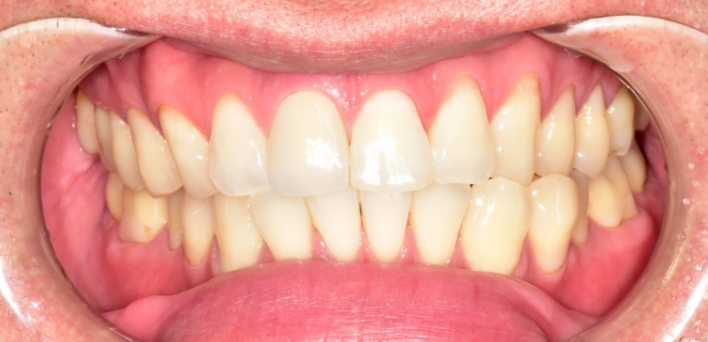

※ 더서울치과의원은 의료법을 준수하며 위 케이스는 실제 환자의 동의를 얻은 사례로 치료 전, 후가 동일한 환경에서 촬영되었습니다.

환자 케이스에 따라 부작용이 발생할 수 있습니다. 이 부분은 의료진의 충분한 상담과 체크를 통해 예방하고 줄일 수 있습니다.

[심미치료 부작용] 시술 후 치아 시림, 보철물 파손 등의 부작용이 발생할 수 있어 개인별 치아 상태에 따른 정확한 진단과 사후 관리가 중요합니다.